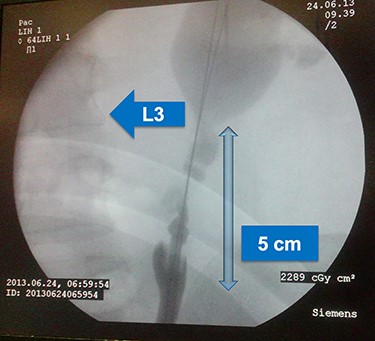

This is a case of 48-year-old man Hypertensive on medication who underwent bilateral percutaneous nephrolithotomy 10 years ago for bilateral renal stones. Patient was referred to our center as a case of left ureteric injury post Flexible URS for left middle and upper ureteric stones and was managed with left DJ stent. Abdominal CT scan showed stones in the left ureter with no leak (Fig. 1). Two months later, we decided to perform retrograde pyelography (RGP) and eventually ureteroscopy in order to clear his stones. RGP showed an invagination of mid-ureter about 4–5 cm (Fig. 2). A guidewire was passed under fluoroscopy guidance. Stones were removed and endoscopic exploration revealed ureteral intussusception (Fig. 3). DJ stent was inserted, and 6 weeks later, we performed a nuclear scan (MAG3) that showed obscure drainage from the left kidney. Therefore, ureteral reconstruction with ileal interposition was our option to overcome this complication. Patient underwent the surgery uneventfully and was followed up after surgery for 6 months and was pain free with no significant hydronephrosis or change in renal function.

Retrograde pyelogram showing invagination of mid ureter for about 4–5 cm, lumbar vertebra 3 is shown for orientation.